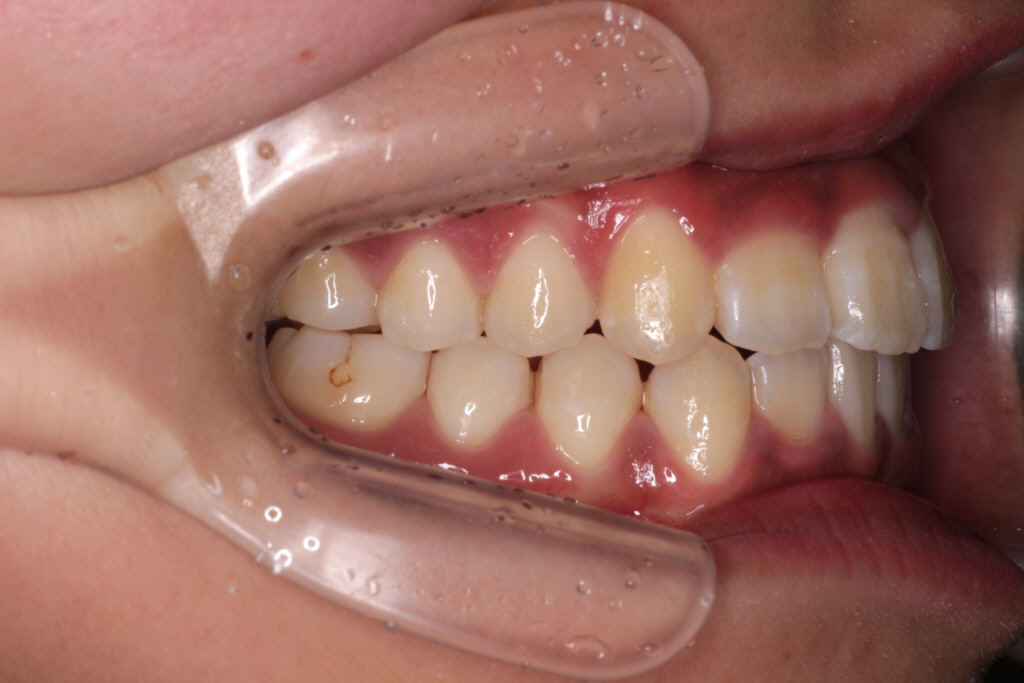

初診時のお口の中の状態です。

上の前から2番目の歯が下の歯列より内側にあり叢生です。

側方の上下の咬合関係が理想の上1本に対して下2本の理想的な噛み合わせではない。

歯列の幅がせまい。